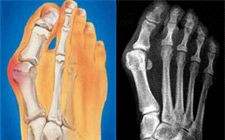

Τα κότσια είναι μια διαταραχή του άξονα του μεγάλου δακτύλου του ποδιού που συνήθως συνοδεύεται και από διόγκωση της άρθρωσης του δακτύλου. Σχηματίζεται τόσο από τα οστά του πρώτου δακτύλου του ποδιού όσο και από τον ορογόνο θύλακο που καλύπτει την πρώτη μεταταρσοφαλαγγική άρθρωση.

Καθώς το κότσι μεγαλώνει, η άρθρωση αρχίζει να προεξέχει προς την εσωτερική πλευρά του ποδιού, με αποτέλεσμα να τρίβεται πάνω στα παπούτσια. Συνήθως τα κότσια συνοδεύονται από στροφή του δακτύλου, καθώς και από παραμόρφωση με σφυροδακτυλία του δεύτερου δακτύλου, ενώ όχι σπάνια συνυπάρχουν και κάλοι πάνω στο ίδιο το κότσι ή στους άλλους δακτύλους του ποδιού.